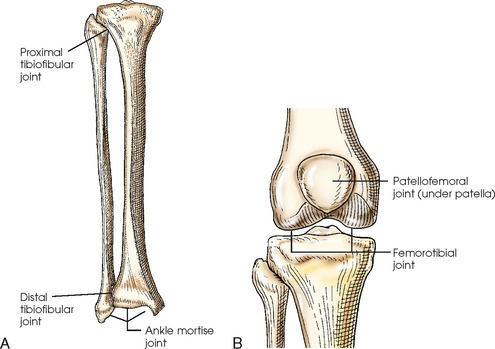

The ankle joint is commonly called the ankle mortise, or mortise joint. It is formed by the articulations between the lateral malleolus of the fibula and the inferior surface and medial malleolus of the tibia (Fig. 6-13, A). The mortise joint is often divided specifically into the talofibular and tibiofibular joints. These form a socket type of structure that articulates with the superior portion of the talus. The talus fits inside the mortise. The articulation is a synovial hinge type of joint. The primary action of the ankle joint is dorsiflexion (flexion) and plantar flexion (extension); however, in full plantar flexion, a small amount of rotation and abduction-adduction is permitted. The mortise joint also allows inversion and eversion of the foot. Other movements at the ankle largely depend on the gliding movements of the intertarsal joints, particularly the one between the talus and calcaneus.

The fibula articulates with the tibia at its distal and proximal ends. The distal tibiofibular joint is a fibrous syndesmosis joint allowing slight movement. The head of the fibula articulates with the posteroinferior surface of the lateral condyle of the tibia, which forms the proximal tibiofibular joint, which is a synovial gliding joint (see Fig. 6-13, A).

The patella articulates with the patellar surface of the femur and protects the front of the knee joint. This articulation is called the patellofemoral joint; when the knee is extended and relaxed, the patella is freely movable over the patellar surface of the femur. When the knee is flexed, which is also a synovial gliding joint, the patella is locked in position in front of the patellar surface. The knee joint, or femorotibial joint, is the largest joint in the body. It is called a synovial modified-hinge joint. In addition to flexion and extension, the knee joint allows slight medial and lateral rotation in the flexed position. The joint is enclosed in an articular capsule and held together by numerous ligaments (see Figs. 6-9 and 6-13, B).